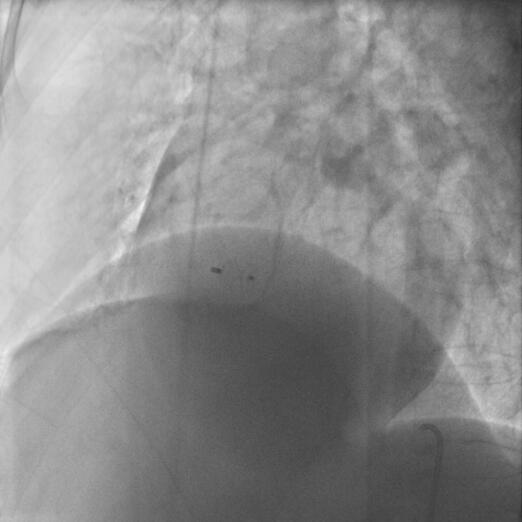

根据患者目前的心导管检查结果提示为轻度肺动脉高压,心室水平左向右分流,尚不存在双向分流,仍为动力型肺动脉高压期,尚有手术时机可行介入或外科手术治疗。因经胸超声心动图显示室间隔缺损位置、大小及与主动脉瓣、房室瓣的关系适合行介入封堵治疗,故该患者行介入封堵治疗。于室间隔缺损破口处置入对称型室间隔缺损封堵器(直径7mm),复查左心室造影无残余分流。术中及术后超声心动图检查封堵器置放完好(图2-12),未见过隔血流信号。无主动脉瓣及二尖瓣反流。心脏听诊杂音消失。

图2-12 介入封堵术后留置的封堵器